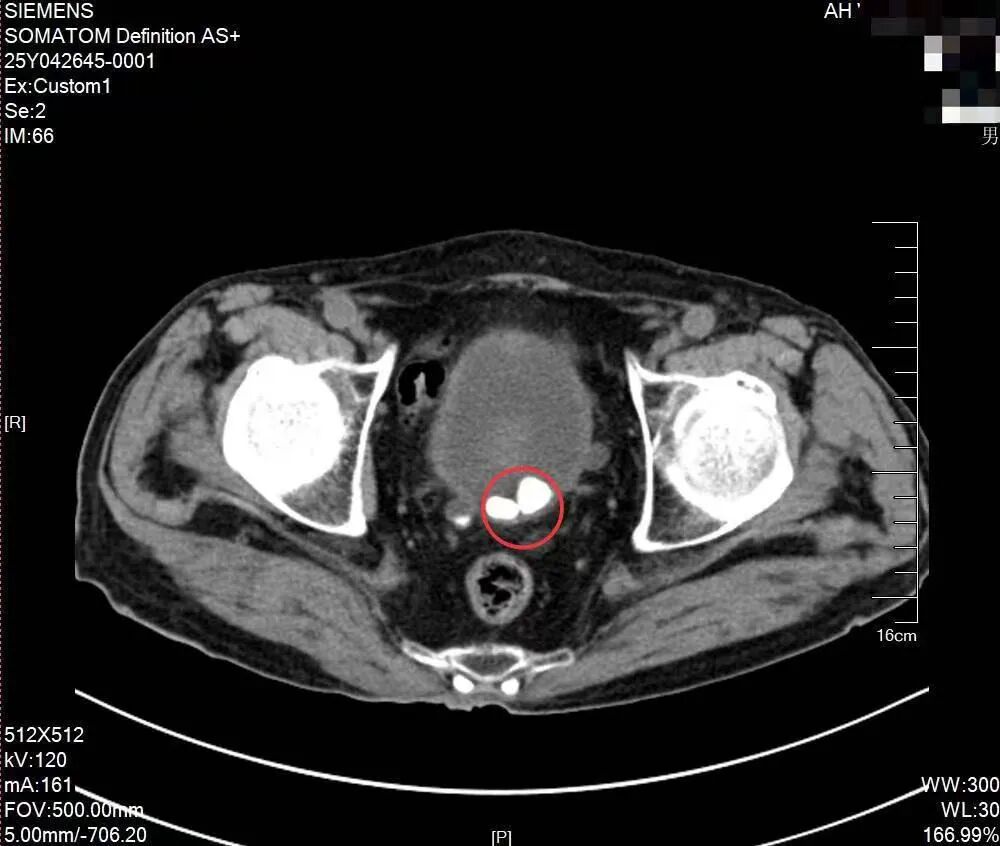

92岁老人膀胱里长了结石

92岁的李爷爷平时精神矍铄,身体硬朗,总是乐呵呵的。然而,最近有一个“难言之苦”困扰着他——排尿困难、中断,同时伴有血尿,让他颇为烦恼。在家人陪伴下来到皖北总院泌尿外科就诊,主治医生王宁宁仔细查体,并结合超声检查,确诊患者膀胱内有多个膀胱结石,为了有效控制病情避免进展恶化,建议手术治疗。

虽说膀胱结石手术本身并不复杂,但是高龄患者的手术常常是个高危、棘手的区域,考虑到患者高龄,患有膀胱结石,合并有泌尿道感染,同时有前列腺恶性肿瘤个人史、肺血栓栓塞症、冠状动脉粥样硬化性心脏病、肺气肿、尿路感染等基础疾病,对手术的承受能力较低,甚至对麻醉而言,都是极大挑战。术前准备、麻醉耐受、感染康复,每一道都是难关。李虎主任协同黄志强副主任医师及王宁宁主治医师,制定了严谨的治疗方案:腰硬联合麻下实施经尿道膀胱镜膀胱激光碎石取石术。

经过充分的术前准备后,患者被推进了手术室。手术中,医生团队与麻醉手术医护团队默契配合,膀胱结石被钬激光碎成小米粒般大小的一堆,然后从尿道中冲出,手术过程仅26分钟,且无出血。患者术后恢复良好,无发热,未觉腰痛。